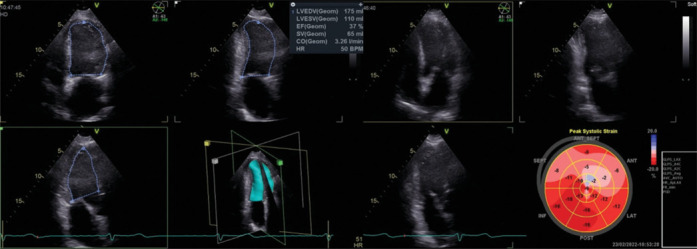

Methods: This prospective observational study included eighty recently diagnosed HFrEF patients with left ventricular ejection fraction (LVEF) ≤35%, prescribed the four pillars of guideline-directed medical therapy, and uptitrated to the maximally tolerated doses. The study included two groups: the ARNI group included forty patients prescribed ARNI, and the ACEI group included forty patients prescribed ACEI. All patients underwent two- and three-dimensional (2D and 3D) echocardiography to assess baseline parameters, including indexed left ventricular (LV) volumes and 2D and 3D GLS, at baseline and after a 6-month follow-up period.

Results: Both groups had no significant differences regarding demographic data and echocardiographic findings at baseline. After a 6-month follow-up period, there was a significant reduction in LV-indexed volumes in the ARNI group (P < 0.001) and indexed left atrial volumes (P = 0.013) compared to the ACEI group. There was a significant improvement in the ARNI group regarding LVEF (P = 0.011), 2D GLS (P < 0.001), and 3D GLS compared to the ACEI group, but no significant change in the LV mass index. Multivariate regression analysis showed that the use of ARNI, absence of diabetes mellitus, and a higher baseline GLS (above-9.1%) are independent predictors for the occurrence of reverse remodeling (defined as an increase in LVEF ≥5%).

Conclusion: The inclusion of ARNI in the pharmacotherapy of HFrEF patients is an independent predictor of LV reverse remodeling, as observed in a significant improvement in both 2D and 3D volumetric echocardiographic parameters, improved LVEF and longitudinal LV systolic function, represented in 2D and 3D GLS. Baseline 3D GLS and not LVEF or 2D GLS can help predict the occurrence of reverse remodeling in HFrEF patients.